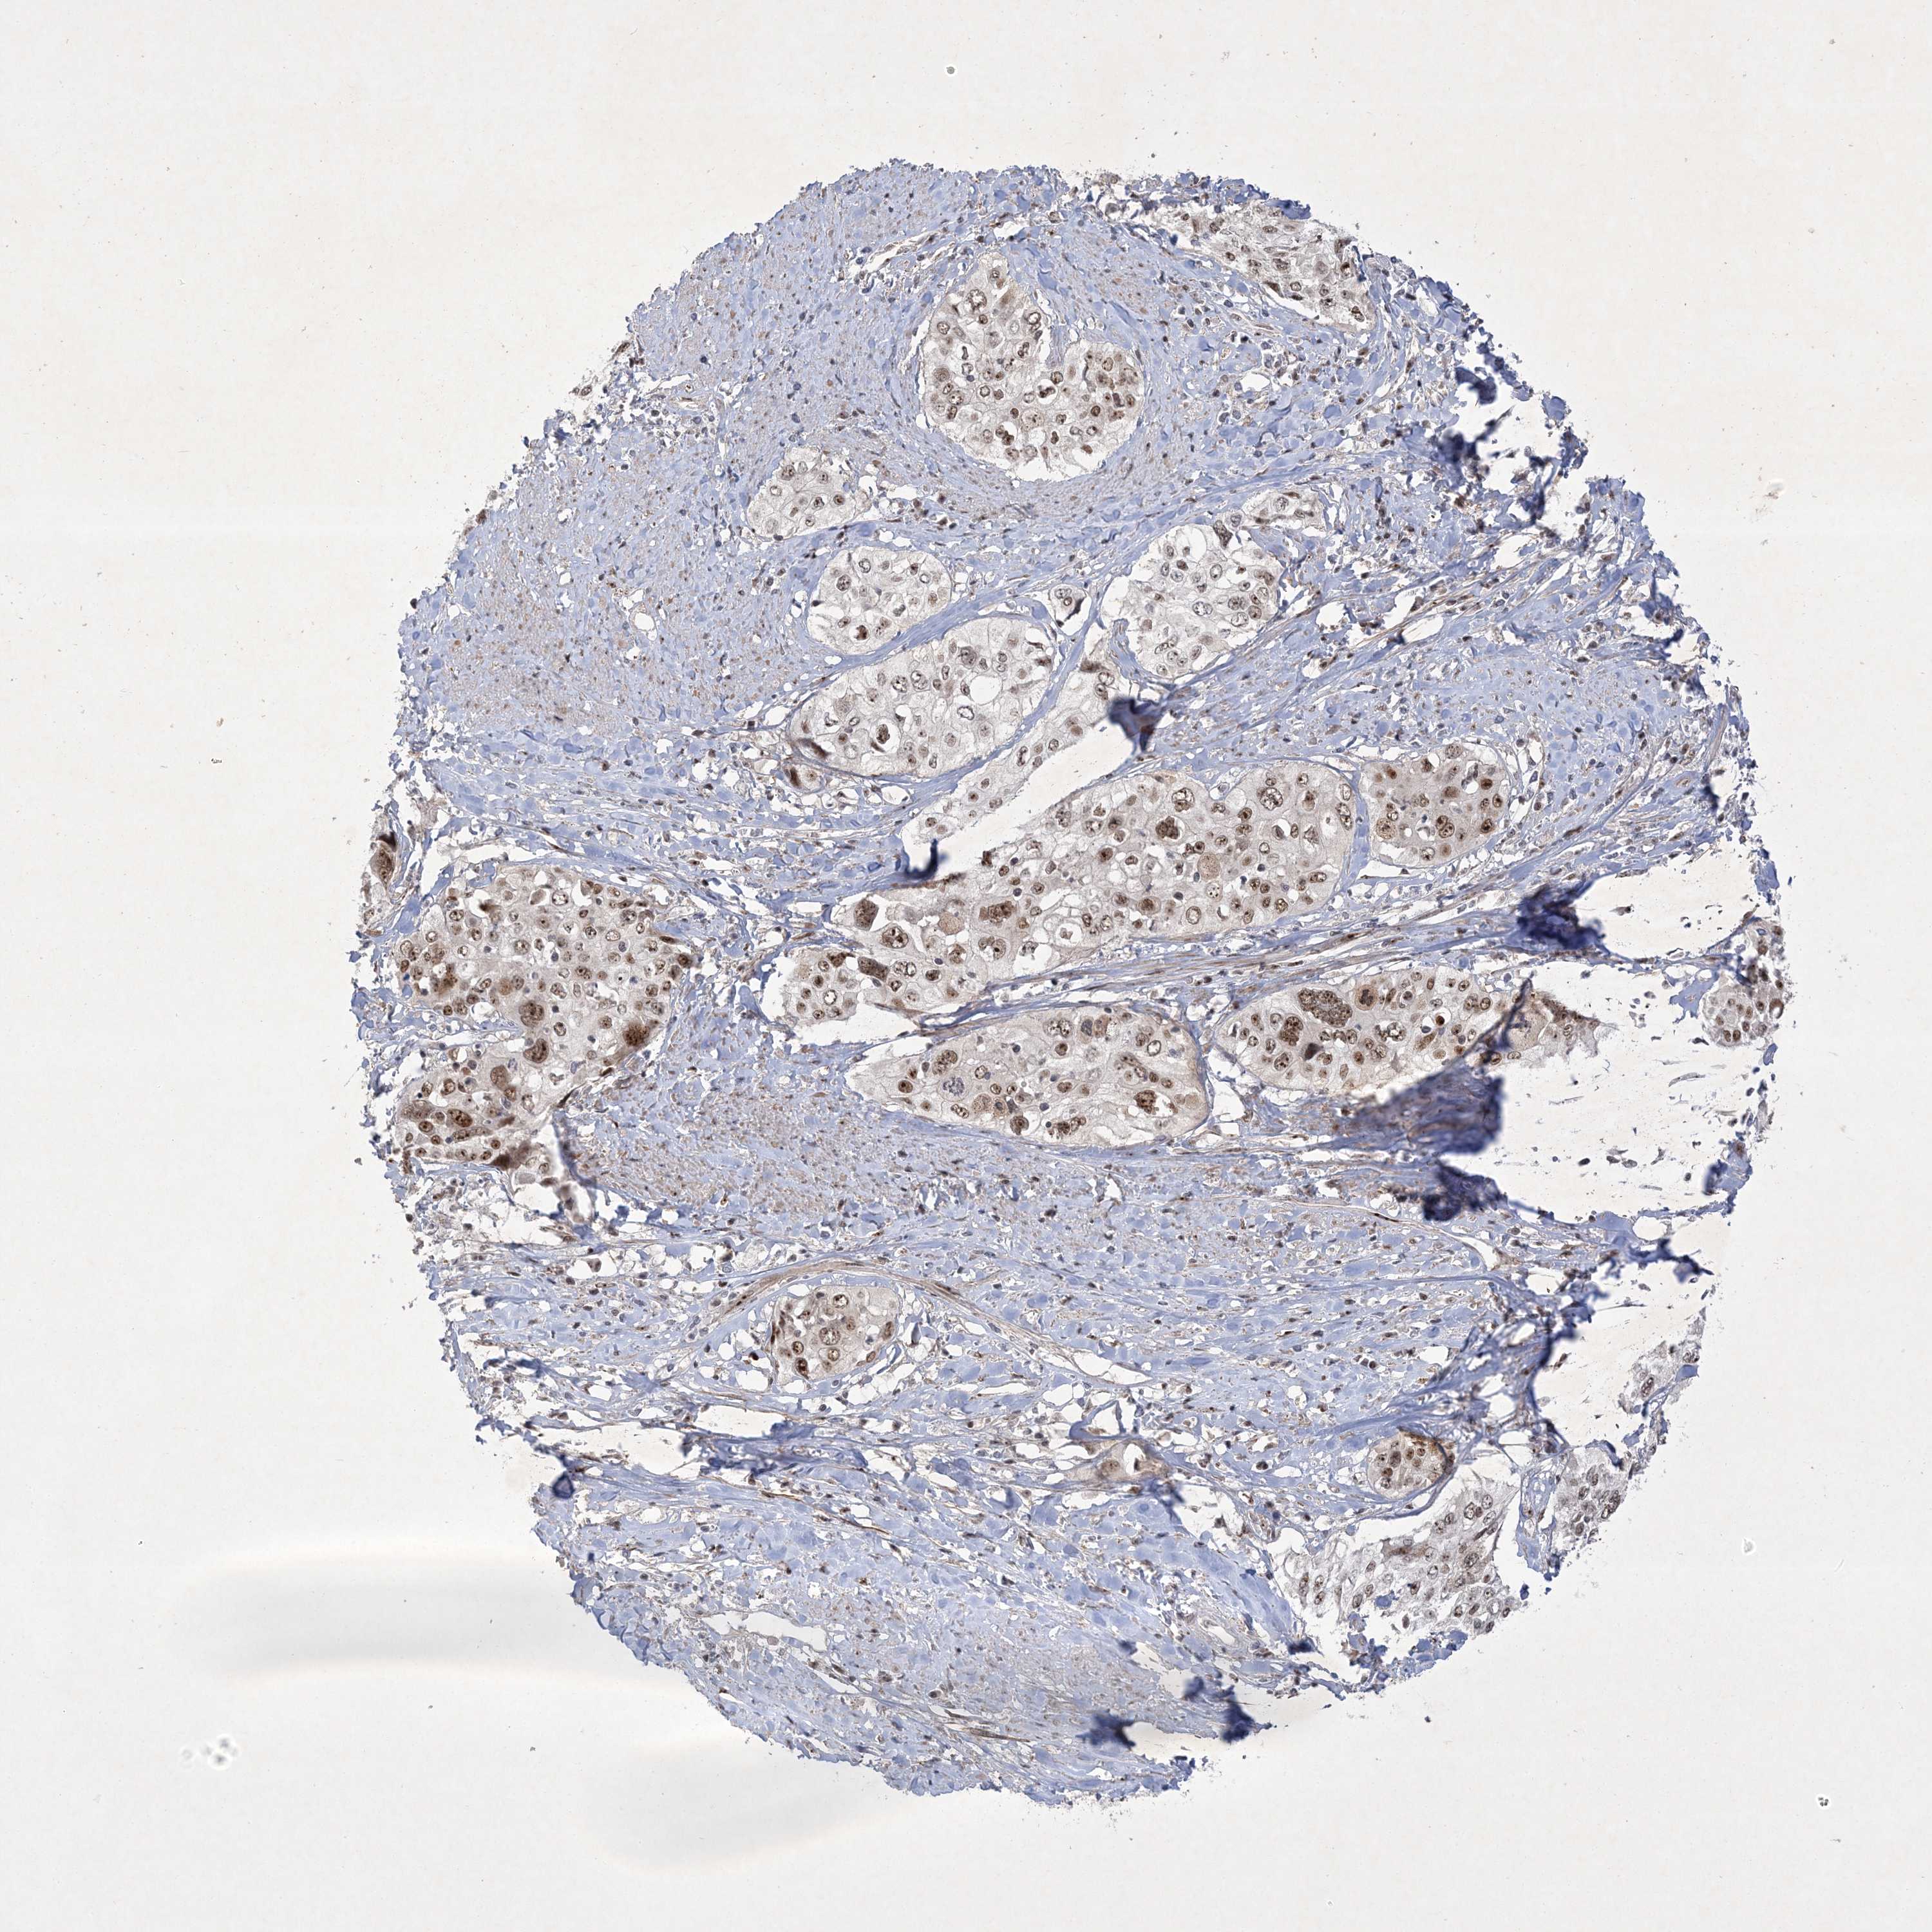

CERVICAL CANCER - Protein expressioni

A mouse-over function shows sample information and annotation data. Click on an image to view it in a full screen mode. Samples can be filtered based on level of antibody staining by selecting one or several of the following categories: high, medium, low and not detected. The assay and annotation is described here.

Note that samples used for immunohistochemistry by the Human Protein Atlas do not correspond to samples in the TCGA dataset.

Antibody stainingi

Antibody staining in the annotated cell types in the current human tissue is reported as not detected, low, medium, or high, based on conventional immunohistochemistry profiling in selected tissues. This score is based on the combination of the staining intensity and fraction of stained cells.

Each image is clickable and will lead to virtual microscopy that enables deeper exploration of all samples and also displays staining intensity scores, fraction scores and subcellular localization as well as patient and tissue information for each sample.

Antibody HPA036295

Antibody HPA036296

Staining

High

Medium

Low

Not detected

Intensity

Strong

Moderate

Weak

Negative

Quantity

>75%

75%-25%

<25%

None

Location

Nuclear

Cytoplasmic/membranous

Cytoplasmic/membranous,nuclear

Squamous cell carcinoma, NOS

Adenocarcinoma, NOS